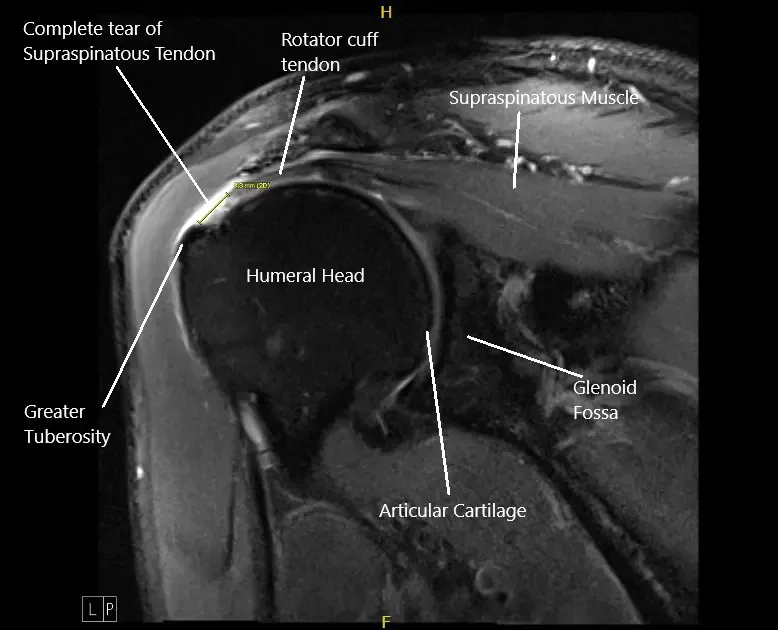

MRI image of the left shoulder showing a complete tear of the rotator cuff.

Radiological studies of the left shoulder suggested a complete tear of the supraspinatus tendon with 8 mm of medial retraction, infraspinatus, and long head biceps tendinosis, subacromial/subdeltoid, and subcoracoid bursitis, AC arthrosis, and degeneration of the superior posterior superior labrum.